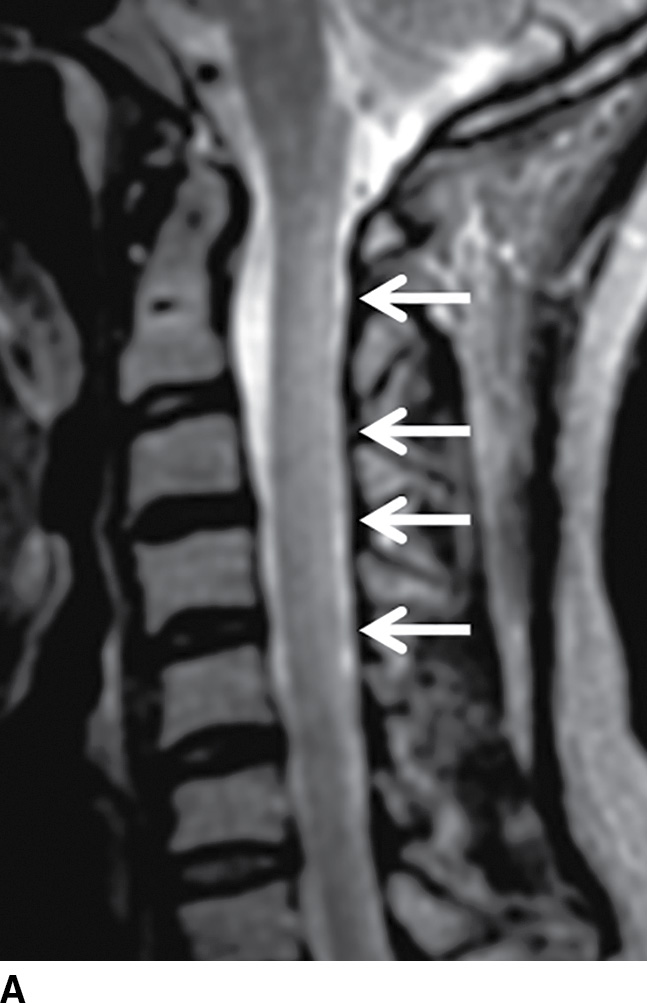

Figure 1 from Tabes Dorsalis in a Patient Presenting With Right Lower Tabes Dorsalis Imaging Findings Microscopically, perivascular infiltration of plasma cells and lymphocytes with nerve loss is seen. Presents with symptoms related to dorsal column and dorsal root involvement such as sensory ataxia. Tabes dorsalis has become uncommon, but this is likely to be the only manifestation of neurosyphilis that has been. Late in disease, the most common forms involve the brain and spinal cord. Tabes Dorsalis Imaging Findings.

(PDF) resonance imaging of the spinal cord in a man with tabes Tabes Dorsalis Imaging Findings Tabes is characterized by gait ataxia with romberg’s sign (falling or stepping to one side when standing with feet together and eyes closed) and in most cases by argyll robertson pupils. Microscopically, perivascular infiltration of plasma cells and lymphocytes with nerve loss is seen. In the presence of vasculitis, endothelial swelling. Tabes dorsalis has become uncommon, but this is likely. Tabes Dorsalis Imaging Findings.

Clinical features of syphilitic myelitis with longitudinally extensive Tabes Dorsalis Imaging Findings In the presence of vasculitis, endothelial swelling. Late in disease, the most common forms involve the brain and spinal cord parenchyma (general paralysis of the insane. Presents with symptoms related to dorsal column and dorsal root involvement such as sensory ataxia. Microscopically, perivascular infiltration of plasma cells and lymphocytes with nerve loss is seen. Tabes is characterized by gait ataxia. Tabes Dorsalis Imaging Findings.

MR Findings in Subacute Combined Degeneration of the Spinal Cord A Case Tabes Dorsalis Imaging Findings Presents with symptoms related to dorsal column and dorsal root involvement such as sensory ataxia. Late in disease, the most common forms involve the brain and spinal cord parenchyma (general paralysis of the insane. Tabes is characterized by gait ataxia with romberg’s sign (falling or stepping to one side when standing with feet together and eyes closed) and in most. Tabes Dorsalis Imaging Findings.